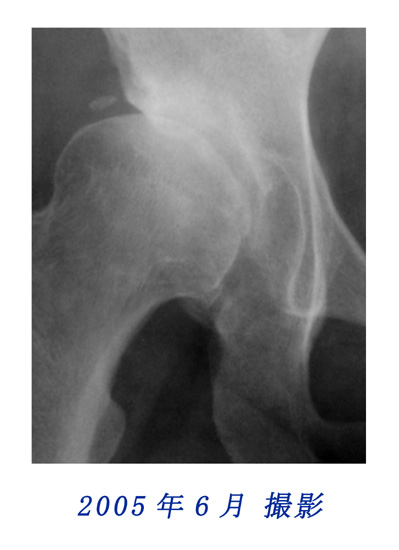

右股関節の変化(部分拡大)

2003年と2005年に撮影されたレントゲン写真中、右の股関節にも顕著な変化を認められました。

右股関節の変化比較用

2003年と2005年のレントゲン写真の股関節部を拡大して重ねました。写真にカーソルを重ねると2003年と2005年の写真が入れ替わります。股関節の変化を観察してください。